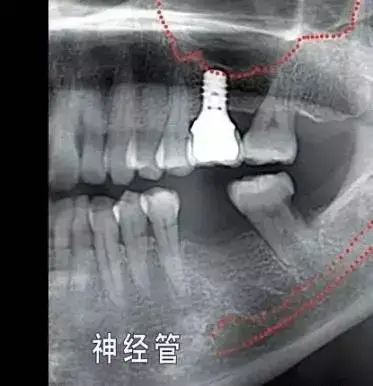

吴女士种植带冠后的牙片显示,种植体就位精准,受力均衡